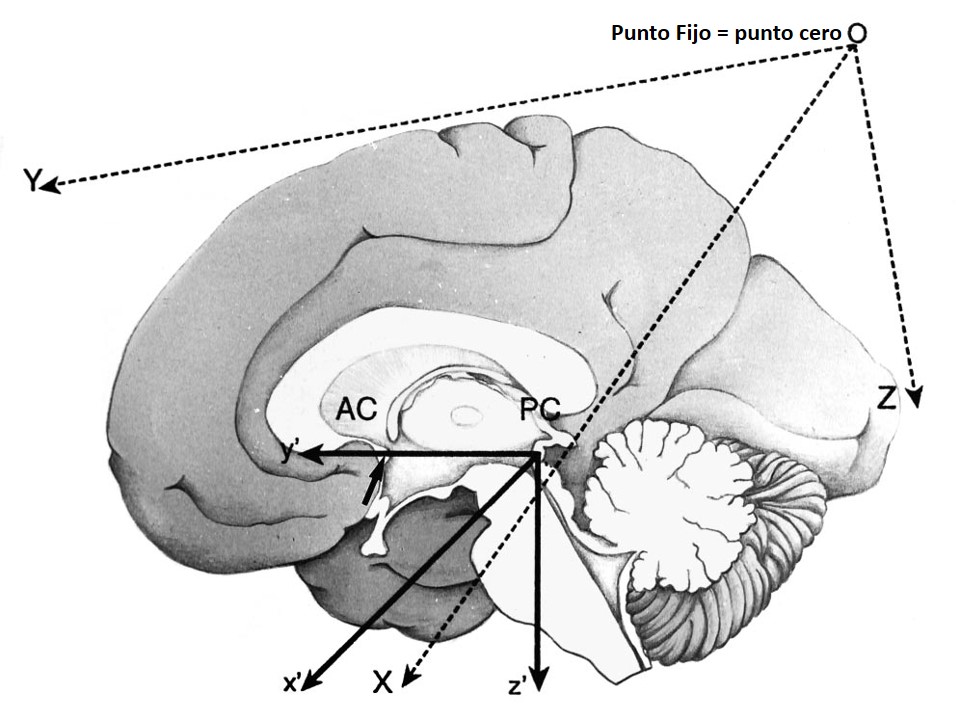

Metodología Estereotáctica o Estereotaxia